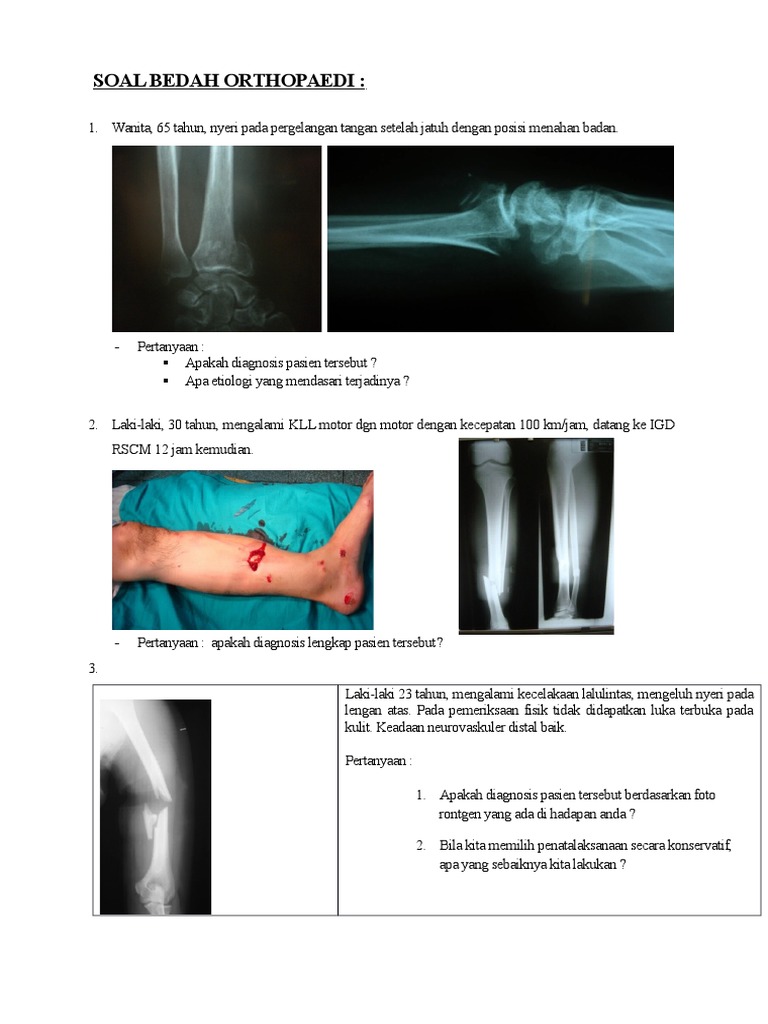

Soal Bedah Orthopaedi